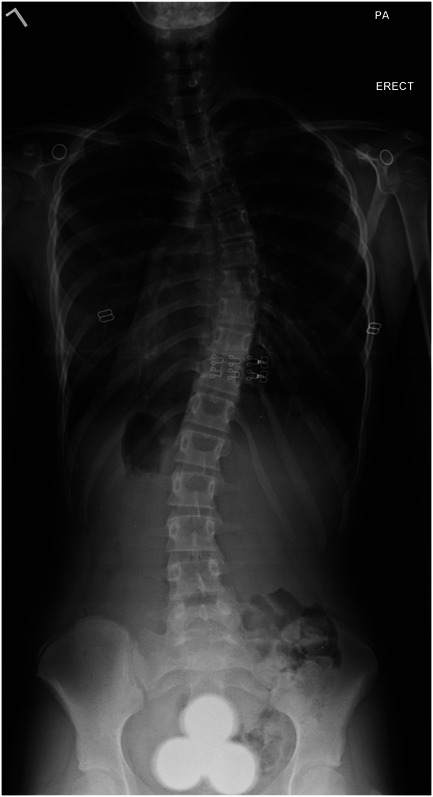

背景:椎体栓系术(VBT)为特发性脊柱侧凸患者提供了另一种治疗方法。我们提交了最终的食品和药物管理局VBT研究器械豁免(IDE)研究结果。方法:回顾性分析2011 - 2015年间Lenke IA/B型曲线患者行VBT的临床资料。前瞻性地收集临床、影像学、围手术期和并发症资料。结果:57例患者入组,平均年龄12.4±1.3岁,随访6.6±1.6年(范围3.0 ~ 10.2年)。术前胸椎Cobb角为40.4±6.8°,2年后矫正为14.5±9.0°,最后随访时略微回落至22.1±12.4°。Sanders和Risser的中位数分别为3和0。最后随访时,71%(39/56)患者骨骼曲线≤30°,98%(55/56)患者骨骼成熟。没有严重的神经或肺部并发症。然而,10名患者需要13次翻修;2 .需要转化为核聚变。预测用力呼气量和用力肺活量的百分比在最后随访时分别从85%和87%下降到80%和82%。结论:这些最终的IDE结果强调VBT是一种安全、有效的治疗骨骼未成熟的特发性脊柱侧凸患者的方法。然而,并发症和翻修率仍然令人担忧,患者应该得到适当的建议。证据等级:三级。有关证据水平的完整描述,请参见作者说明。

Results: Fifty-seven patients (mean age 12.4 ± 1.3 years) were enrolled and followed for 6.6 ± 1.6 years (range: 3.0-10.2 years). Thoracic Cobb angle measured 40.4 ± 6.8° preoperatively with correction to 14.5 ± 9.0° at 2 years and slight regression to 22.1 ± 12.4° at last follow-up. Median Sanders and Risser were 3 and 0, respectively. At last follow-up, 71% of patients (39/56) had curves ≤30° and 98% (55/56) had achieved skeletal maturity. There were no major neurologic or pulmonary complications. However, 10 patients required 13 revisions; 2 required conversion to fusion. Percent predicted forced expiratory volume and forced vital capacity dropped from 85% and 87%, respectively, to 80% and 82% at the final follow-up.